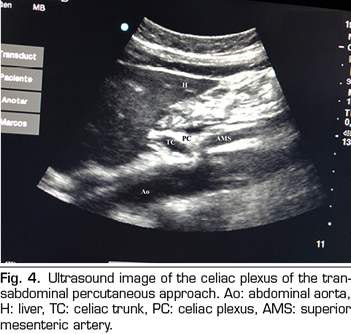

PERCUTANEOUS ULTRASOUND-GUIDED CELIAC PLEXUS NEUROLYSIS

In recent years, ultrasound has made head against fluoroscopy and CT in interventional pain management. The first describing the technique on the celiac plexus was Bhatnagar (31), and it could be performed percutaneously at the patient’s bedside and supine, which gives greater comfort for both the patient and the doctor. However, there are still no randomized controlled trials comparing abdominal ultrasound neurolysis of the celiac plexus versus opioid systemic treatment. The technique is performed using a convex transducer (2-5 MHz), initially placed just below the xiphoid process in the transverse plane, to identify structures, such as liver, stomach, intestine, portal veins, cava and aorta. With the help of the Doppler, we scanned caudally to identify the bifurcation of the celiac trunk in the hepatic and splenic arteries, and more distally in the superior mesenteric artery. Then we rotate the transducer in the longitudinal plane, visualizing in the same image the bifurcation of the aorta in the celiac trunk and in the superior mesenteric artery with the celiac plexus surrounding these structures. The approach is performed in plane, transabdominal, through the liver or stomach, as long as there are no large vessels interfering with the needle path (Figure 4).

No complications have been reported with the percutaneous ultrasound approach; however, the literature in this regard is insufficient to draw conclusions (32).